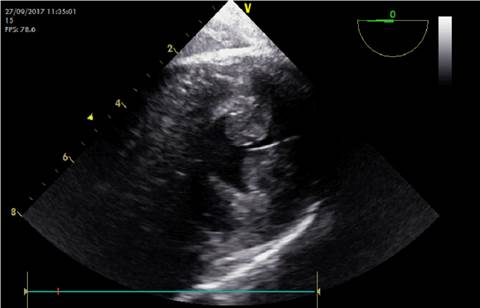

SBP: verse el VI en forma circunferencial con los dos músculos papilares en el plano transgástrico eje corto. Imagen 1 .

SBP: En la imagen en modo B, el músculo papilar anteromedial y posterolateral debían juntarse para considerarse positivo.